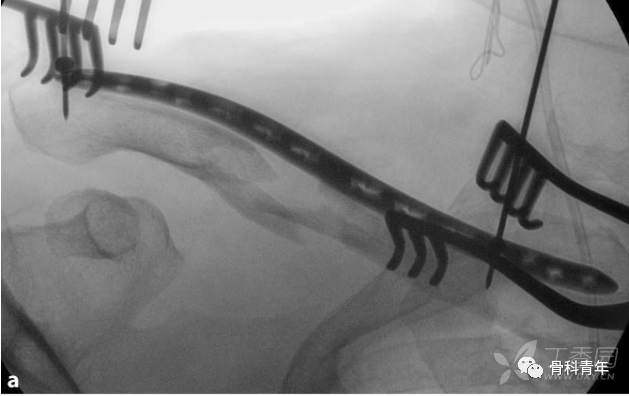

通过两边切口,骨膜剥离子建立骨面隧道,插入钢板,远近端夹持复位或采用Joystick技术复位,复位后先经钢板最外侧孔置入克氏针或皮质螺钉临时固定,复位满意后经钢板内侧孔置入克氏针固定。